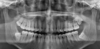

What does the red indicate in the following image?

Maxillary sinus

Q

A

Maxillary tuberosity